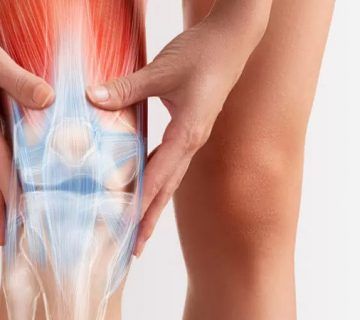

آرتروز زانو و روش های محافظت از آن

آرتروز زانو یک بیماری مزمن و التهابی است که منجر به تخریب و آسیب در سطح مفصل زانو میشود. در این بیماری، درجه فرسایش و سایش ... ادامه مطلب

جراحی تعویض مفصل زانو یا (Total Knee Replacement) این جراحی یکی از رایج ترین و موفق ترین روش های درمان آرتروز شدید زانو است. در این روش، بخش های آسیب دیده مفصل زانو (استخوان، غضروف) با قطعات مصنوعی جایگزین می شوند.